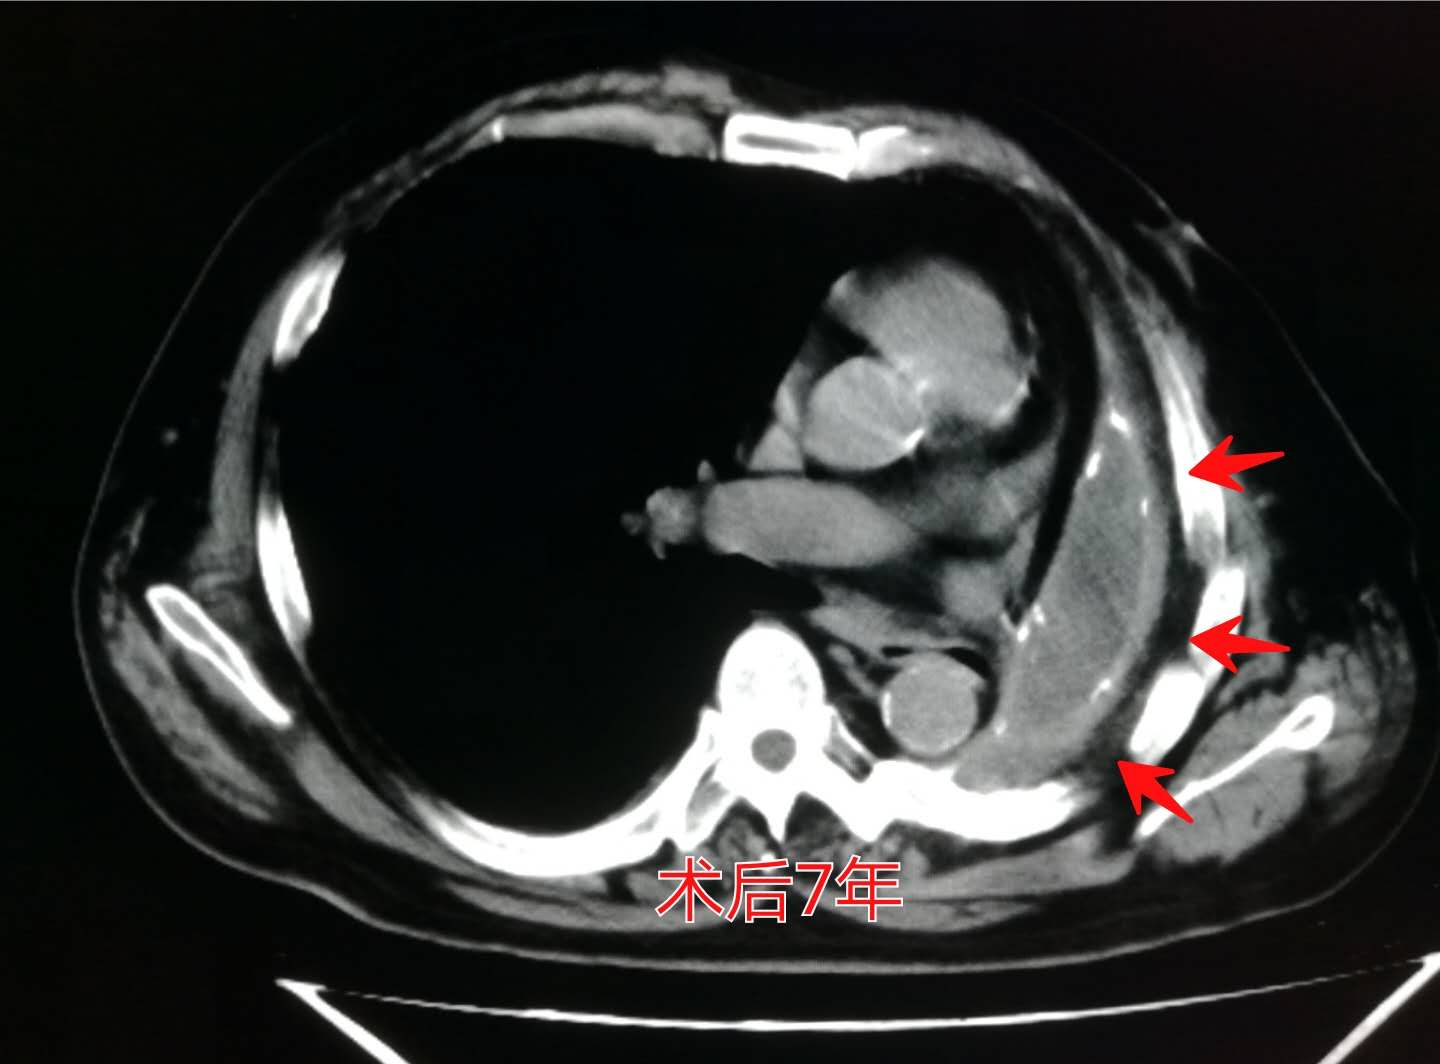

而到今年已经是第7个年头了,最近一次的复查依然良好:

并且我们可以看到,在残腔的周围,已经发生了斑点状的胸膜钙化(白色斑点状影)。

我们上面提到过,随着时间的推移,边缘胸膜可以发生钙化,这一点是吻合的。